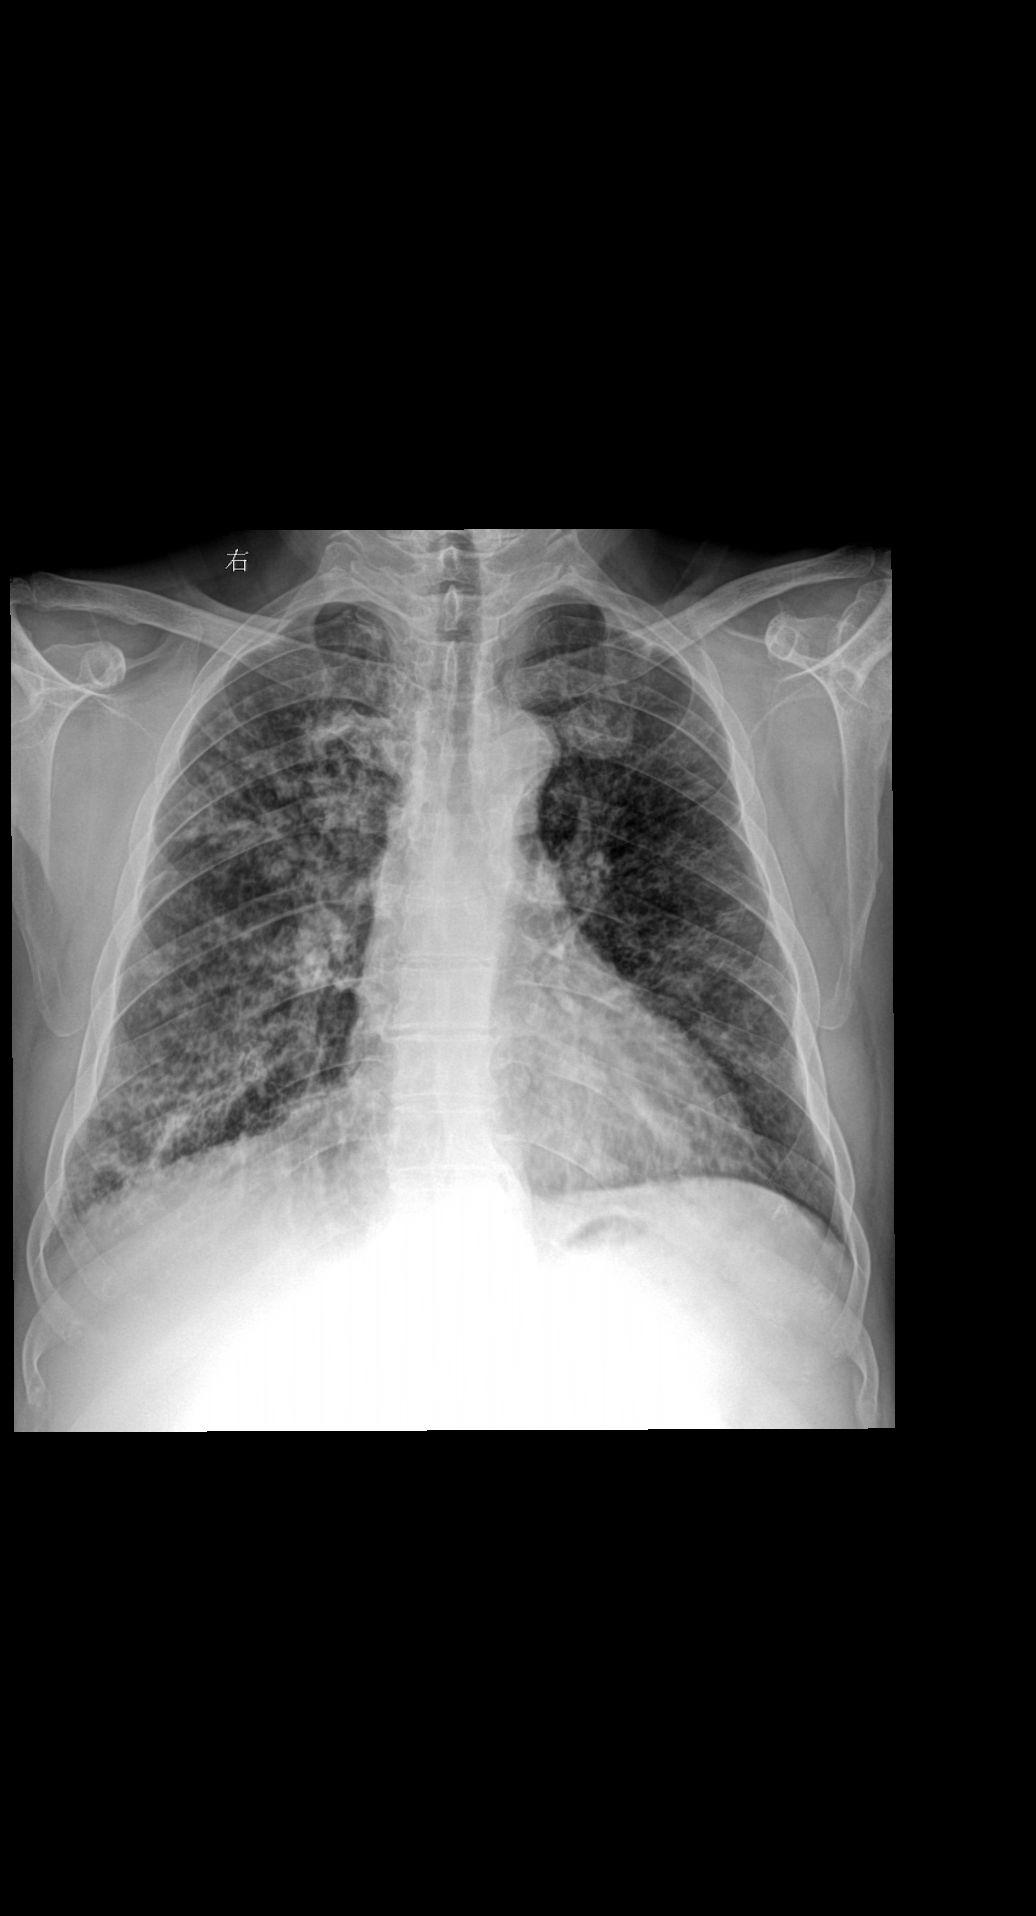

主诉:咳嗽 闷气 男 80y 考虑什么家人们?答案打到评论区